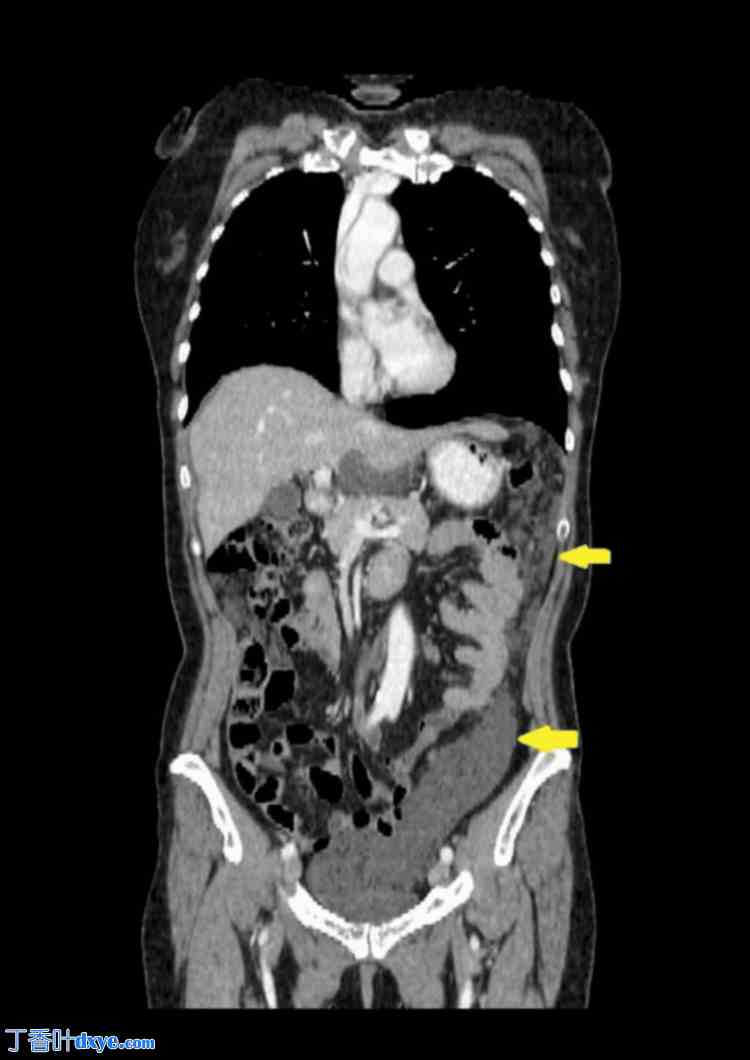

胸部、腹部和盆腔CT扫描(静脉注射造影剂)显示肝周、脾周及盆腔内多处低密度积液(提示为粘蛋白)。在大网膜、小网膜及侧沟内发现聚集性腹膜沉积物,提示腹膜广泛受累。胸部和腹部器官未见其他病理改变。扫描区域淋巴结未肿大。未见骨质破坏或成骨细胞活动征象(图1-4)。

图 2. 腹膜转移及腹部和盆腔局部积液的 CT 成像。

箭头所示为右侧胆管转移灶。